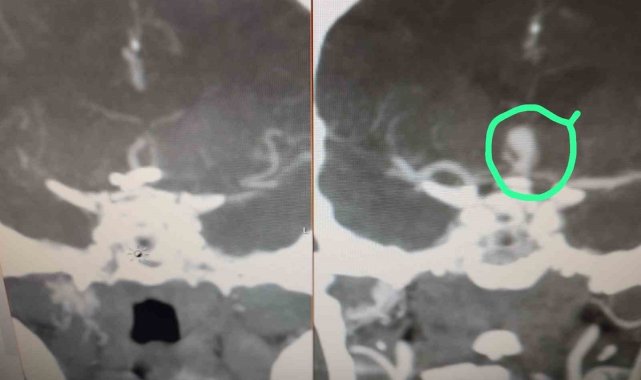

Beyninde anevrizma tespit edilen hasta, Serik Devlet Hastanesi'nde kaş üzerinden minimal bir kesi ile gerçekleştirilen operasyonla sağlığına kavuştu. Beyin ve sinir cerrahisi uzmanları Op. Dr. Ömer Elçik ve Op. Dr. Salim Tekir tarafından uygulanan yeni yöntem sayesinde hastanın ameliyat sonrası sürecinin hem daha konforlu geçtiği hem de estetik açıdan iz bırakmadığı bildirildi. Geleneksel beyin cerrahisinde kullanılan geniş kesiler yerine uygulanan modern teknik, özellikle yüz bölgesinde iz kalmasını istemeyen hastalar için önemli bir gelişme olarak değerlendiriliyor. Operasyonun ardından hasta kısa sürede taburcu edildi.

Antalya'nın Serik ilçesinde beyninde baloncuk (anevrizma) tespit edilen hasta, Serik Devlet Hastanesi'nde kaş üzerinden minimal bir kesi ile gerçekleştirilen operasyonla sağlığına kavuştu.